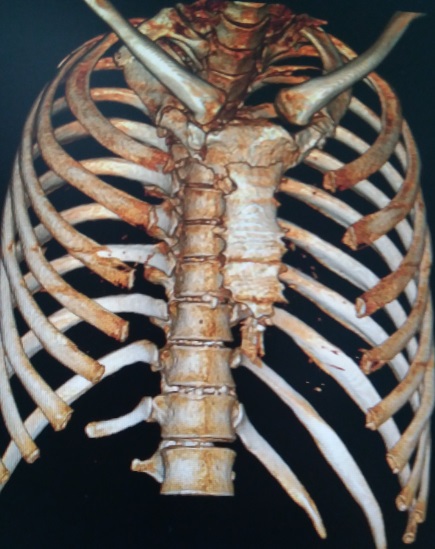

术前行X线检查,提示胸椎骨折固定术征象,左侧第2、3后肋骨折。行CT检查,提示胸骨两处骨折,其中上位骨折位于胸骨角,骨折上半胸骨嵌入下半胸骨后方。三维重建提示胸骨骨折,前胸壁凹陷畸形。

图3,三维重建,胸骨两处骨折。

图4,三维重建:上位骨折处明显凹陷。